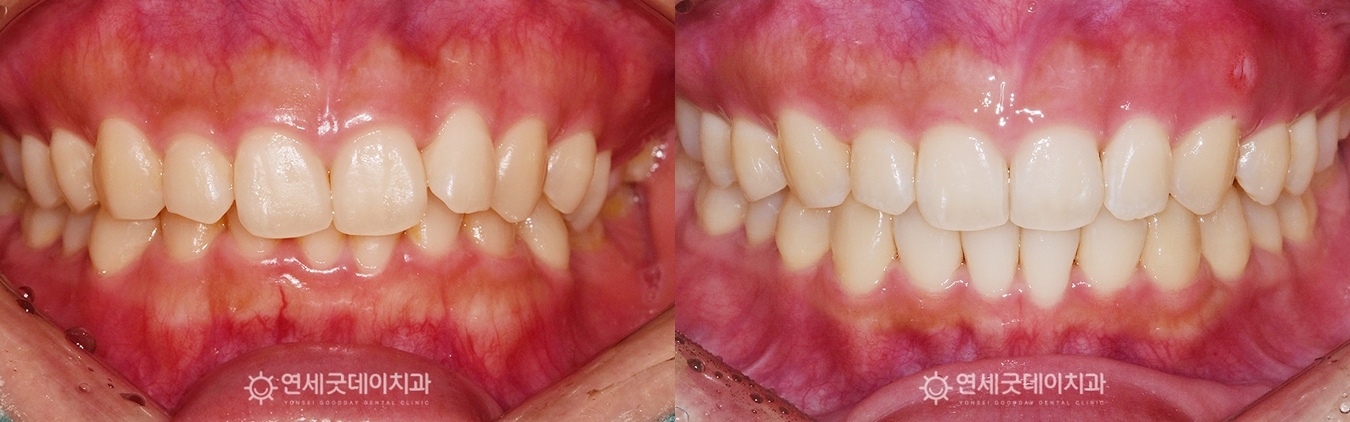

하지만 #35 치아가 쓰러지면서 또 한 가지 주의 깊게 살펴볼 부분은 ‘과개교합’입니다. ▲ 치료전 안모 (촬영시기 : 2022년 10월) 환자분은 과개교합, 쓰러진 치아로 인한 인접치의 정출 따라서 부분교정의 한계점에 대해 충분히 설명드린 후 ▲ 과개교합 교정 후 엑스레이 (촬영시기 : 2024년 3월) 약 1년 6개월의 인비절라인 교정이 마무리되었습니다. 기울어진 치아는 정상적인 위치로 올바르게 세워졌으며 ▲ 과개교합 교정 종결 (촬영시기 : 2024년 3월) 윗니의 높이와 각도가 개선되면서 아랫니가 정상적으로 드러나고, ▲ 치료 후 안모 (촬영시기 : 2024년 3월) 웃을 때마다 과도하게 드러났던 거미스마일도 ▲ 치료전후 비교 (촬영시기 : 2022년 10월 / 2024년 3월) 과개교합은 턱관절 불편감이나 저작 불편으로 이어질 수 있어 과개교합을 교정함으로써 증상을 완화하고 그동안 치료 받으시느라 고생 많으셨습니다. ^^ ※ 모든 사진은 본인의 동의를 얻어 동일조건에서 촬영하였으며 |